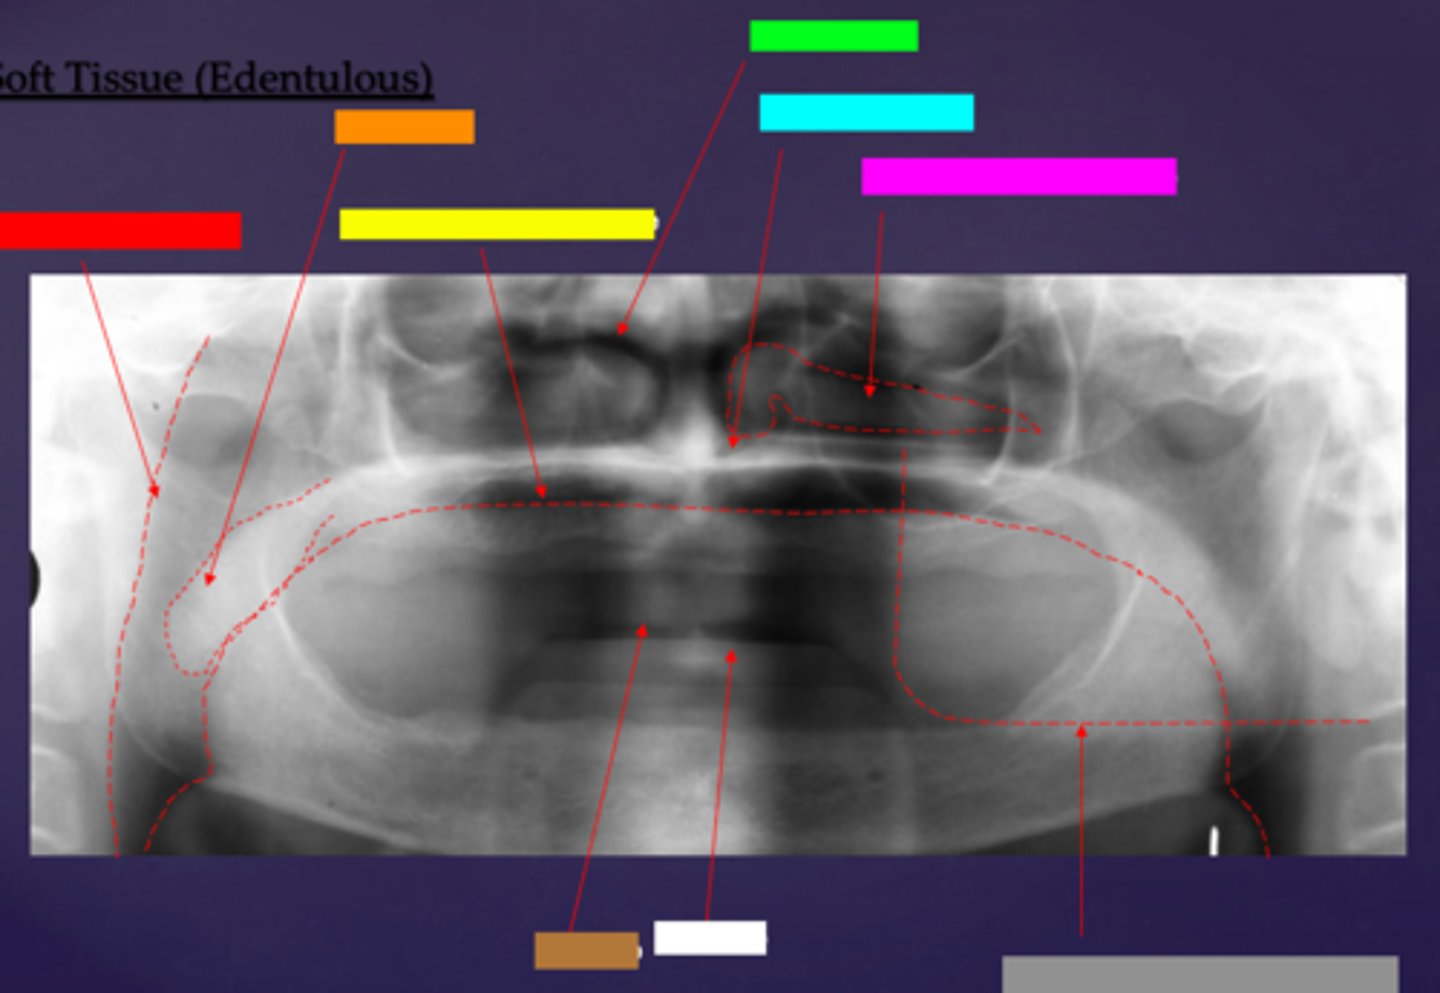

ID the soft tissue anatomy indicated by the arrow pointing from the red box:

ala of nose

ID the soft tissue anatomy indicated by the arrow pointing from the orange box:

nasal septum

ID the soft tissue anatomy indicated by the arrow pointing from the yellow box:

columna (the septum separating the nostrils)

ID the soft tissue anatomy indicated by the arrow pointing from the green box:

tragus

ID the soft tissue anatomy indicated by the arrow pointing from the light blue box:

ear lobe